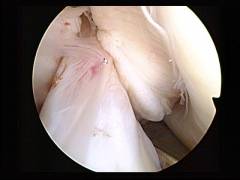

Артроскопия плечевого сустава: ход операции

- Осуществляют пункцию плечевого сустава: в него вводят иглу от шприца и подают через нее физиологический раствор. Это нужно для того, чтобы полость сустава растянулась, и в нее можно было ввести артроскоп, не повредив хрящи.

- Затем делают надрез на коже, и суставную полость прокалывают троакаром. Вводят артроскоп и осуществляют осмотр. Через артроскоп в полость сустава подают физиологический раствор для промывания и улучшения видимости.

- При необходимости делают дополнительные проколы и вводят через них хирургические инструменты.